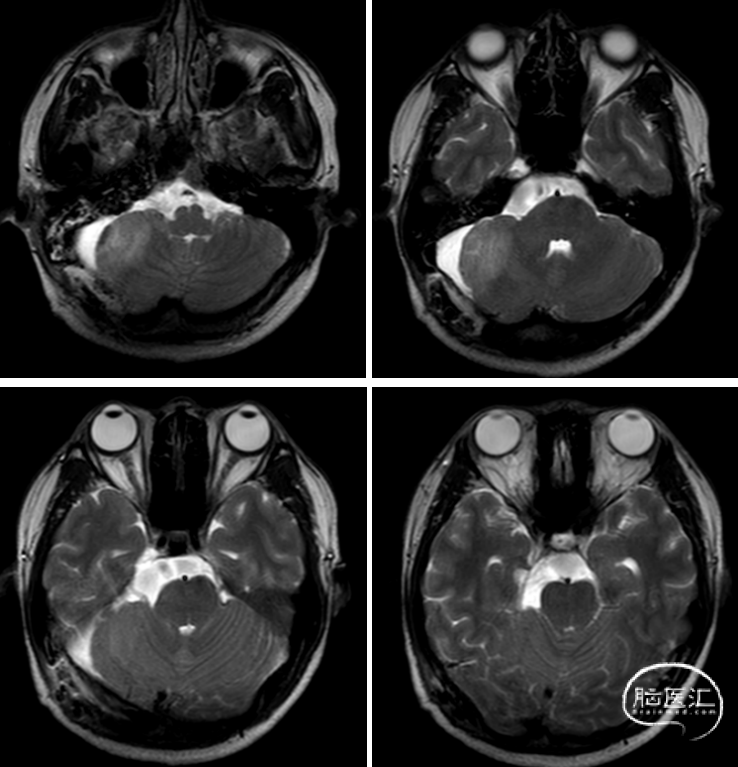

查体:右侧听力下降。

术后MRI